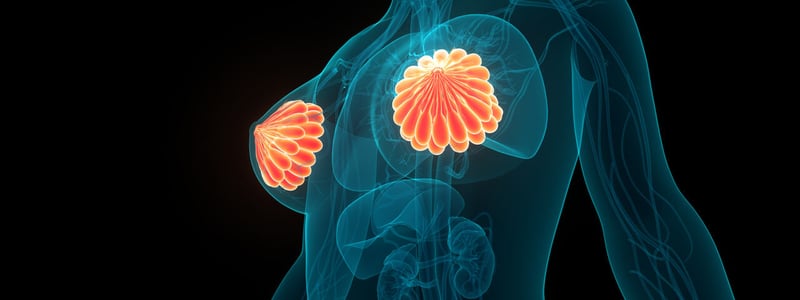

Jede Brust (Mamma) besteht aus 10 bis 20 Drüsenlappen mit jeweils zahlreichen Drüsen.

Die Brustdrüsen (Mammae) sind paarig angelegte Organe am Oberkörper jedes Menschen. Die Brustanlage ist bei Männern und Frauen gleich, über die Ausbildung der reifen Brust entscheidet lediglich der Einfluss von Östrogenen. Jede Brust besteht aus 10 bis 20 Lappen, die aus vielen Milchdrüsen zusammengesetzt sind. Die Ausgänge der Milchdrüsen münden in der Brustwarze (Mamille). Die Drüsenlappen sind eingebettet in Binde- und Fettgewebe. Dieses entscheidet auch über die individuelle Größe der Brust. Das Brustgewebe unterliegt hormonellen Einflüssen und verändert sich im Rahmen des Menstruationszyklus sowie in der Schwangerschaft.

- Die weibliche Brust besteht aus zahlreichen Drüsen, die in Drüsenlappen organisiert sind.

Die Brust besteht aus Drüsenlappen (Lobi glandulae mammariae), deren Drüsengänge zur Brustwarze führen. Die Drüsenlappen liegen eingebettet in Binde- und Fettgewebe (Interlobuläres Stroma). Die Brustwarze (Mamille)besteht aus einem Warzenvorhof (Areola mammae), dessen Farbe sich durch stärkere Pigmentierung von der umgebenden Haut abgrenzt .In der eigentlichen Mamille (Papilla mammaria) münden alle Ausführungsgänge der Milchdrüsen. Die Mamille hebt sich normalerweise leicht über das Hautniveau ab. Ist dies nicht der Fall und liegt die Brustwarze auf Hautniveau oder leicht eingesunken, kann das Stillen erschwert sein.

Die weibliche Brust besteht aus vielen Brustdrüsen, die in 10 bis 20 Lappen pro Seite angeordnet sind. Die Lappen sind eingebettet in Binde- und Fettgewebe.